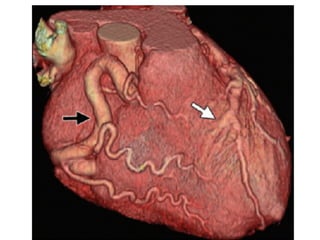

Kawasaki Disease

A

Kawasaki Disease A • first described in Japan in 1967 by Tomisaku Kawasaki • Etiology unknown – thought to be infectious vs. autoimmune • Aneurysm or ectasia develops in 15%–25% of untreated children within 3–6 months • Cardiac sequelae may develop as many as 10– 21 years after the acute phase of the disease

• By 2years after the onset of Kawasaki disease, 49% of the patients have spontaneous regression of aneurysms • LM (12%), RCA (3%), both arteries in 8%